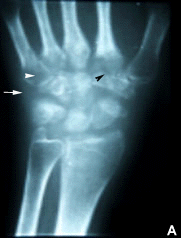

| Aumento de la densidad de partes blandas (flecha), osteopenia yuxta-articular (Cabeza de flecha blanca), erosiones en los primeros metacarpianos y huesos del carpo (cabeza de flecha negra). | Estudio normal |